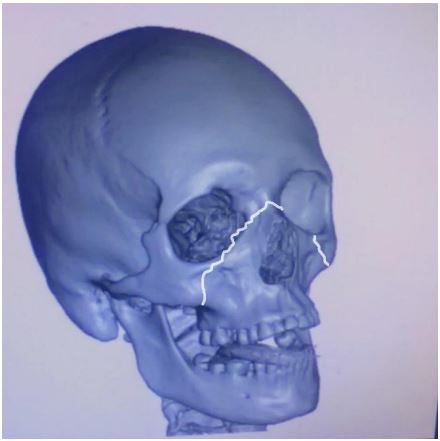

Paciente vítima de trauma facial. A tomografia mostra traço de fratura segundo indicado na imagem abaixo.

Trata-se de uma fratura do tipo: